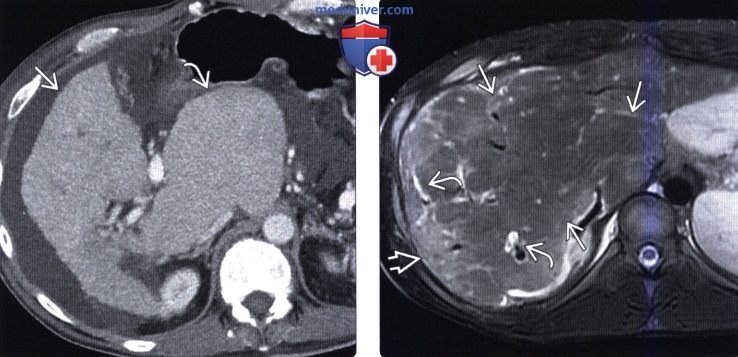

Фотографии и изображения, связанные с симптомами первичного склерозирующего холангита